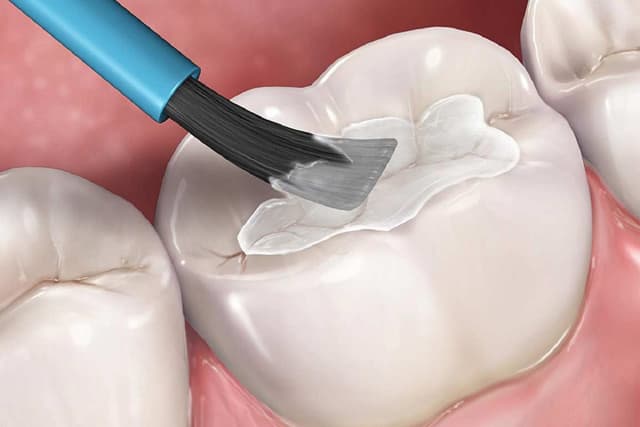

Chữa sâu răng có thể đem lại hiệu quả hay không tùy thuộc nhiều vào sự phù hợp giữa phương pháp bạn chọn và mức độ sâu của răng. Do đó để tìm ra được cách chữa sâu răng phù hợp bạn cần biết rõ răng mình đang sâu ở giai đoạn nào. Bài viết […]

Phát hiện sớm các tổn thương sâu răng và lựa chọn cách chữa sâu răng phù hợp, kịp thời sẽ mang lại kết quả tốt cho quá trình điều trị về cả phương diện thẩm mỹ, chức năng và thậm chí còn giảm khả năng biến chứng tại răng cũng như sức khỏe tổng thể. […]

Sâu răng có thể nói là bệnh lý phổ biến ở mọi lứa tuổi, tùy vào mức độ sâu răng mà bác sĩ sẽ có phương án điều trị khác nhau. Trong đó, hàn răng là một trong những phương pháp được sử dụng nhiều nhất. Vậy thời gian hàn răng sâu có lâu không, […]